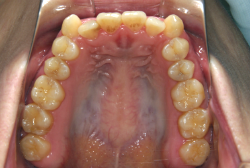

凸凹な歯並びのことを叢生といいます。矯正歯科に来院する患者様の主訴の中で、最も多いのが「配列の凸凹を真っ直ぐにしたい」というものです。歯の大きさと顎の大きさの調和がとれていないことが原因です。

凸凹を主体としたケースの場合、当院の平均治療期間は18ヶ月ですので、このケースは少し長めに経過しました。理由の一つは凸凹の程度がかなり重症だったと言うことですが、もう一つは、右下第2大臼歯が45度くらい前傾していたため、それを整直化させるために時間を要したと考えています。いずれにしても最終結果は大変よい状態と思います。

治療前は並びが乱れて見た目が悪いというのはもちろん問題ですが、歯科医学的に一番困るのは噛み合わせが悪いという点です。上下の犬歯(3番目の歯)は、上下的に離れた位置にあるため接触することができません。つまり歯としては存在していても、歯としては機能していないということです。